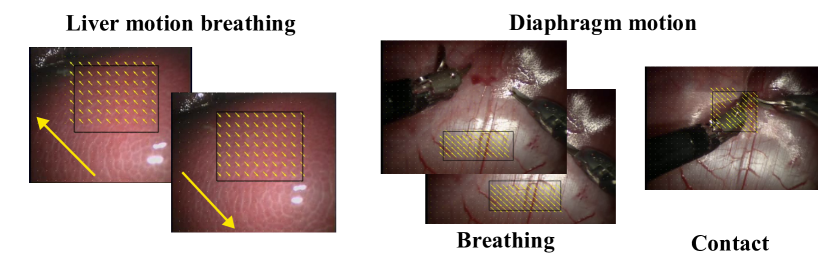

We collect a total of 30 videos, 15 for each of the environments (silicone phantom and ex-vivo real porcine tissue described in 3.1). In addition, we use real surgical videos of natural body motions from the Hamlyn Centre Laparoscopic / Endoscopic Video Datasets [19, 20, 21]. These videos include motion of a liver and a diaphragm due to breathing, and cardiac motion.

The force textures 𝝍subscript𝝍\mathcal{F}_{\boldsymbol{\psi}} provide the solution of the constraint problem for a certain region of interest inside the image. For plotting purposes, for every time instance t𝑡t we normalize the force Ft(𝝍)subscript𝐹𝑡𝝍F_{t}(\boldsymbol{\psi}) using the spatial mean and standard deviation of the region of interest 𝝍𝝍\boldsymbol{\psi}. In addition, to keep the scale across the whole duration Tsuperscript𝑇T^{\prime}, we normalize the force a second time with the temporal mean and standard deviation. We run our model through all the examples and we validate our method by human inspection and visual consistency with the recorded interaction. Furthermore, we calculate the direction and value of the natural forces from the real surgical videos [19, 20, 21]. We make a collection with different examples of these textures in Figure 6. We present the direction and intensity of the forces using yellow arrows and the region of interest is highlighted with a black box.

Figure 6: Force texture maps for different real surgical videos. Both contain the analysis of the natural oscillation generated by breathing. On the diaphragm example in the right, we have the analysis of a contact in addition to the underlying breathing motion.